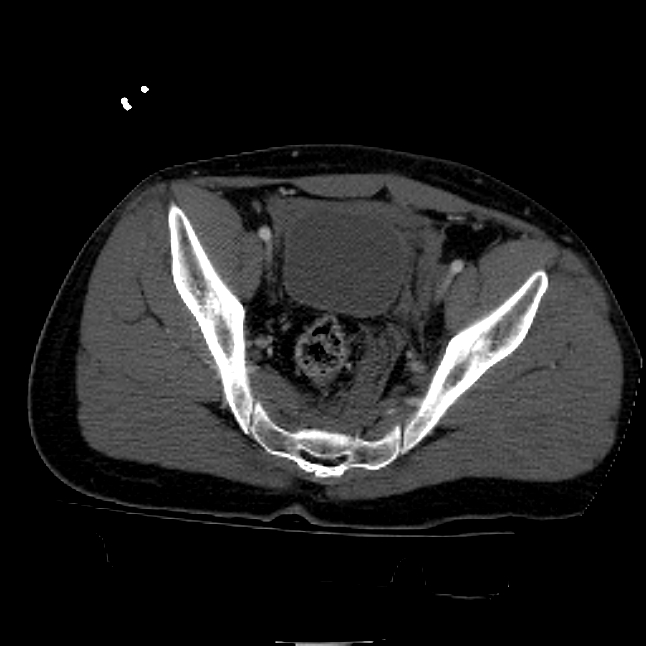

25 yo brittle diabetic, became hypoglycemic and passed out on his motorcycle. Sustained bilateral lateral Hoffa fractures with associated LCL injury on the right and right distal radius fracture. I have questions regarding his pelvic ring/acetabular fracture on the left. Appears to be a very low posterior column fracture with associated posterior wall, marginal impaction. Superior and inferior rami fractures as well on the left giving him a floating segment of inf ramus/ischium/posterior column, but no detectable posterior ring injury. Should the posterior column/posterior wall fracture be addressed surgically because of the marginal impaction? Or is this fracture low enough to be treated non-operatively? I appreciate the input.

It's an interesting case. The plain films show the impaction, but most of the joint looks pretty good. The CT cuts look awful, though.

The impaction is so big I don't think I would ignore it. It IS down low, but it takes up almost the whole southern hemisphere of his joint.